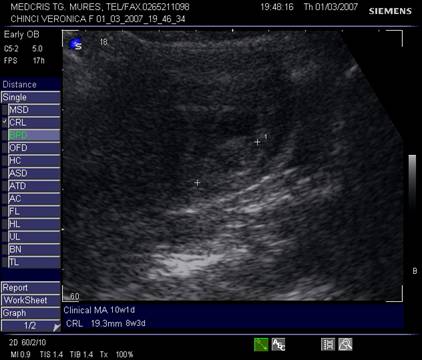

Fig nr. 84. Discrepanta intre CRL (crown rump lenght sau lungimea craniocaudala)

si amenoree, la o sarcina oprita in evolutie

Fi

g nr 8 Cavitate chorionica (anecogena) prea mare, fata de un embrion si vezicula vitelina mici ( hiperecogene, cu una respectiv doua sageti ), la o sarcina oprita in evolutie

Fig. nr. 86.

Sarcina oprita in evolutie cu embrion( intre calipere) situat decliv si putin

lichid amniotic( sageata)